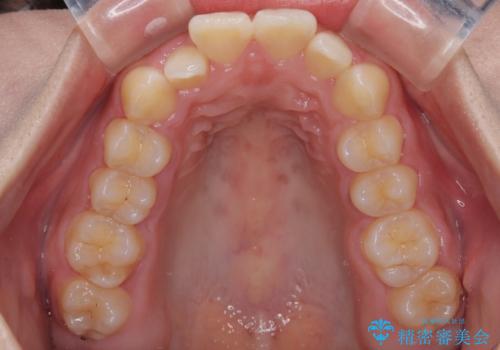

- 前歯のデコボコが気になるでのことで来院された患者様です。

歯列アーチが狭くスペース不足により前歯がデコボコしている状態でした。見た目を改善しつつ、前歯を前方に突出させず、自然な笑顔を目指したいというご希望でした。

治療計画

・アーチを側方に拡大して歯が並ぶスペースを確保

・抜歯は避け、非抜歯での対応